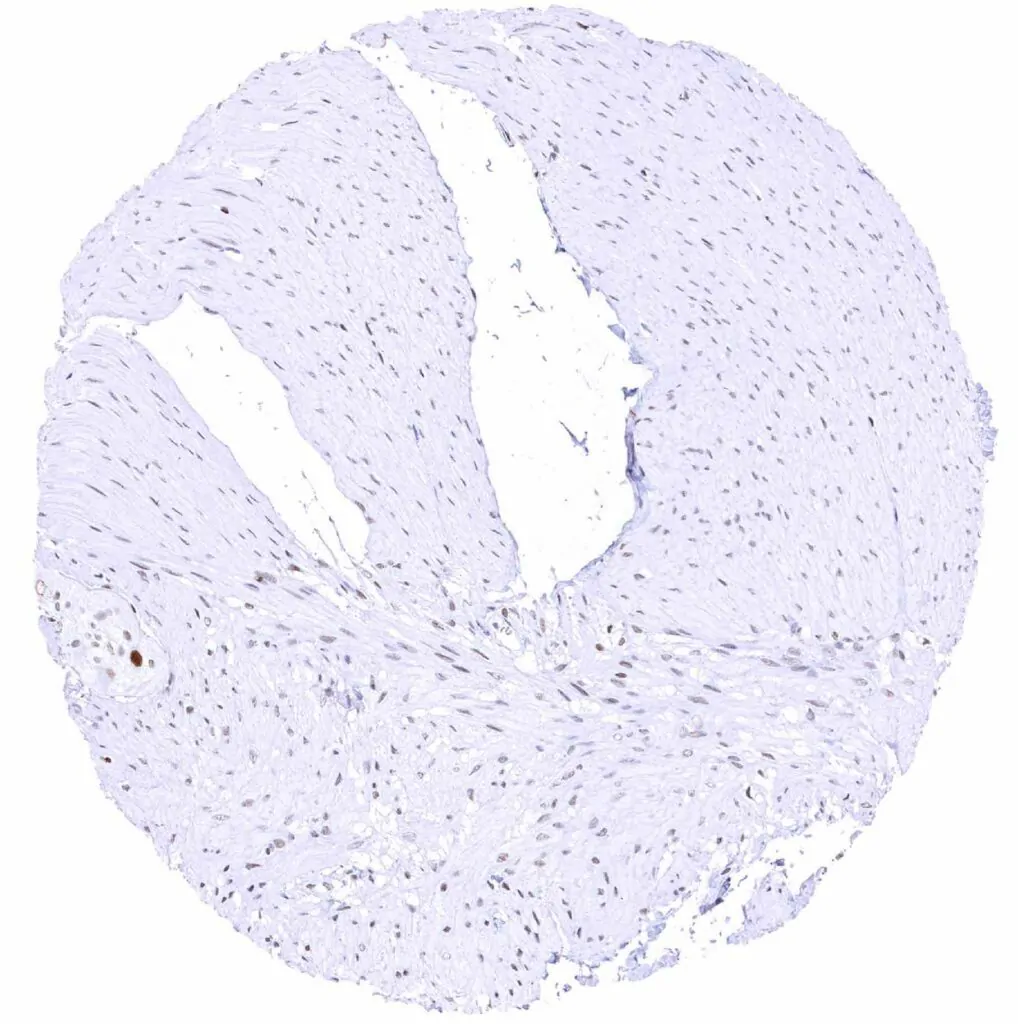

Urinary bladder, muscular wall